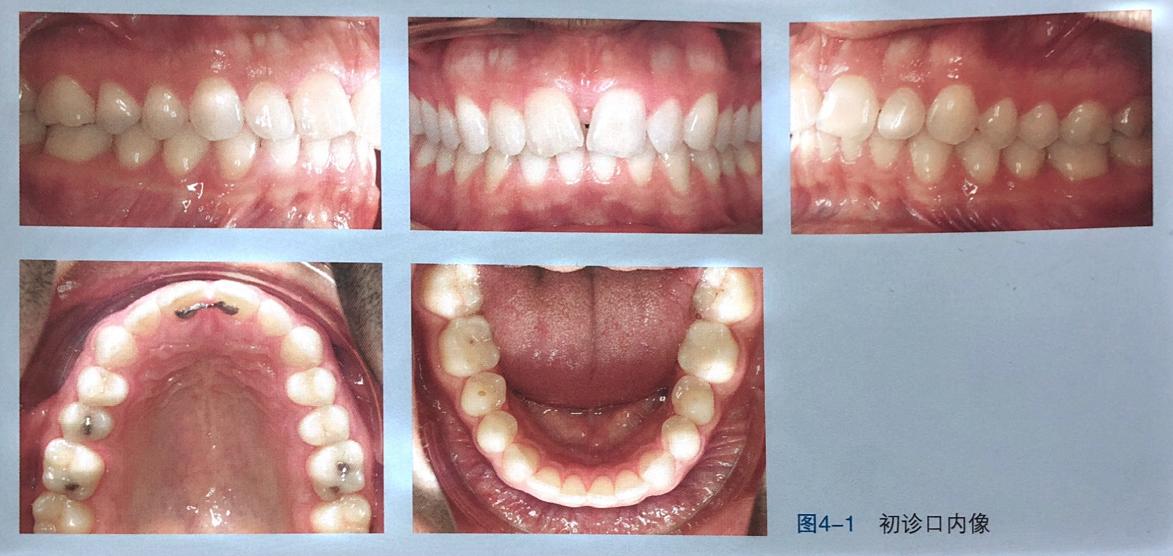

(这个案例患者曾经做过固定矫正,也就是传统矫正。主要问题为中切牙间的黑三角如图)

治疗过程治疗目标是去除黑三角的病因,即解决#11、#21严重的根远中倾斜问题。